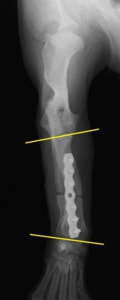

術中において、浅趾屈筋腱を剥離、内方へ牽引し、直接踵骨から第4足根骨までピンを挿入し(あらかじめ細いピンで下穴をあけておくとよい)、テンションバンドワイヤー法を併用し、関節軟骨の掻爬と海綿骨移植を実施しました。

術後レントゲン画像上に癒合が認められるまで約2ヵ月間は、運動を制限する必要があります。